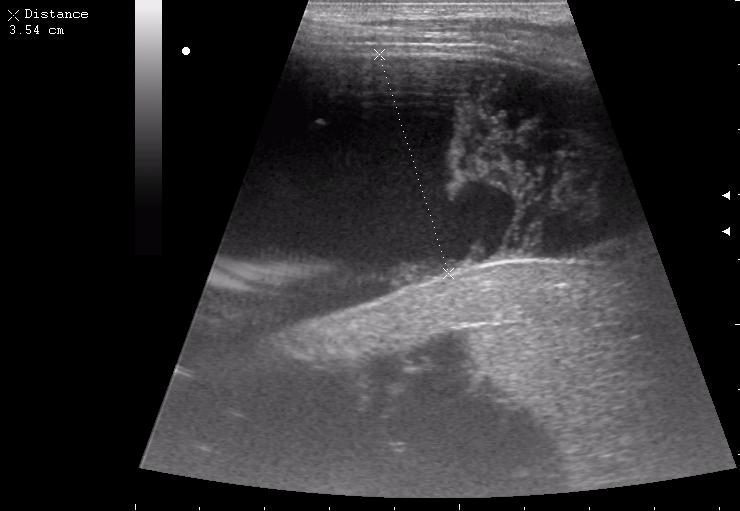

подкапсульная гематома, 7й сегмент<br />лечился методом наблюдения

подкапсульная гематома, 7й сегмент

лечился методом наблюдения

спустя 1 год после травмы<br />(ДЖВП - сопутствует)

спустя 1 год после травмы

(ДЖВП - сопутствует)